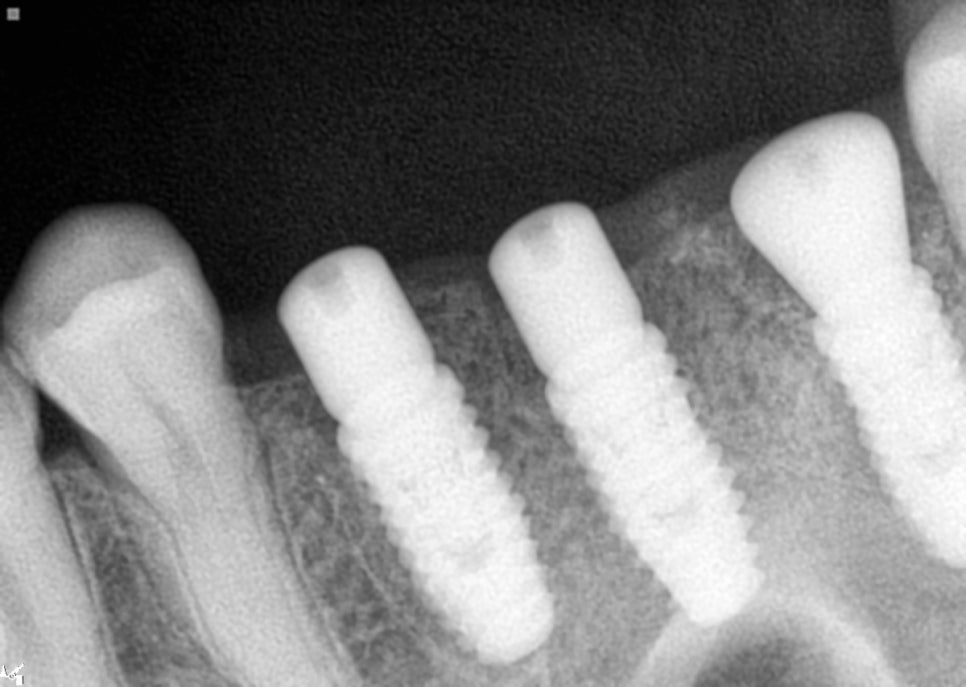

상악동 거상술을 시행한 부분을 보면

오른쪽 위 첫번째와 두번째 큰 어금니 부위는

크레스탈 접근법(crestal approach)을

이용한 상악동 거상술을 진행했습니다.

위쪽 3개 임플란트 식립 완료

임플란트 식립하는 구멍을 통해 상악동막을

거상을 하는 방식인데요.

아래쪽 임플란트

매우 정밀하게 진행을 해야합니다.

측방 접근법에 비해서는 침습자체가 적고

회복이 빠르다는 장점이 있습니다.

각 임플란트 부위마다 적절한 골이식재를

사용했고 인접 치아의 장축과 평행하게

정확한 각도로 식립하는 것이 중요하거든요.